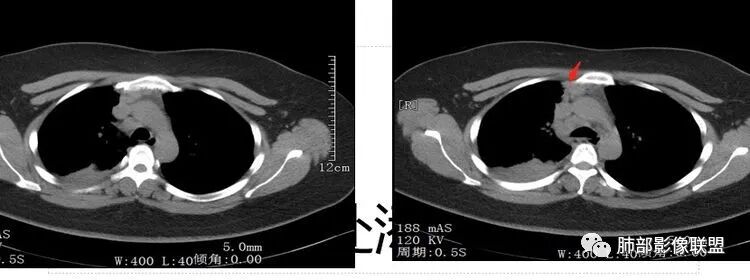

第一个问题:定位

下叶?还是多叶?

因为这个很关键

例如:上叶、下叶、中叶都受累;中、下叶病变;下叶病变不一样。

上、中、下都有,我要看主支气管,如果主支气管没问题,我不考虑阻塞的问题

中下叶有——中间段支气管

下叶——下叶支气管

我们捋一捋病灶的范围

我再捋一捋支气管

右主支气管

上叶支气管

中间段

争议的地方这是上叶?中叶?

说实话图不全

关键点——中间段支气管堵塞处

没有显示

都是以肺内的病变为主

其实关键点在中间段支气管

通过视频显示中间段堵了

支气管腔内占位

远端低强化,提示粘液很多

纵隔淋巴结大